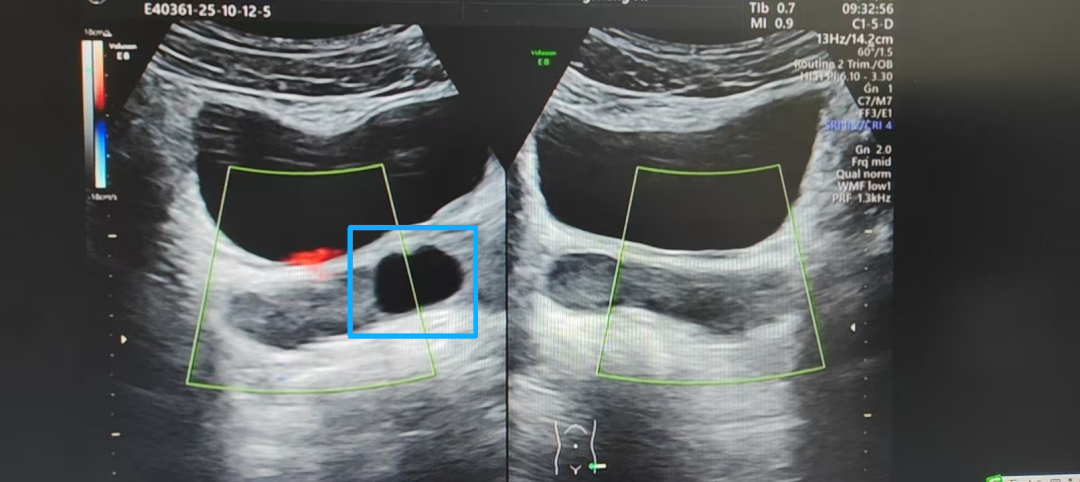

影像清晰显示,吴先生的精囊区域存在异常,一个囊肿样改变形成了“路障”,压迫了射精管,导致这条精子排出的通道发生了不完全性梗阻。精子排出困难,长期淤积、缺氧,最终导致精子失去活力,大量“凋亡”。

超声下的囊肿(蓝框内)